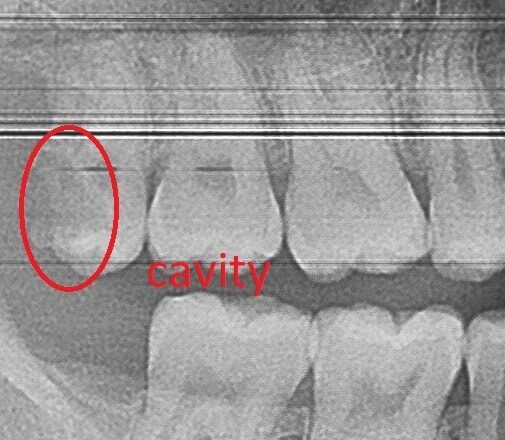

The best way to prevent any dental problem from occurring is good oral hygiene habits at home, plus visiting the dentist twice a year for routine exam and dental cleaning appointments.  Diagnosing and treating dental problems early on, is the best way to prevent a future tooth extraction.  For example, a small dental cavity may destroy a tooth beyond repair if left untreated for too long.  We can often catch cavities before they get big at routine preventative appointments.  Sometimes, our patients can even reverse cavities that are just beginning to for with flossing and using a Fluoride mouthwash.

The best way to determine if a tooth needs to be extracted is to visit your dentist for an accurate diagnosis.  When a tooth is required to be extracted it maybe infected causing pain and/or swelling.  Dental x-rays are required to determine the extend of the tooth damage.  Some very infected and painful teeth can be saved with a root canal and a porcelain crown.  Upon careful examination, the dentist can determine if your tooth can be saved.